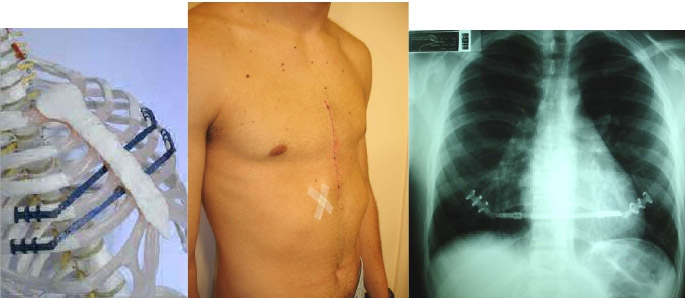

Técnica Operatória Convencional: Esternocondroplastia

Resume-se na ressecção das cartilagens deformadas e com osteotomias (fraturas) transversas do osso esterno corrigido na posição mais anterior possível com fios de aço. Neste tempo cirúrgico, pode-se a inter por uma tela de Marlex (polipropileno) abaixo do esterno, ou barras retro esternais denominadas de Stratos. Ambos mantêm o esterno em sua nova e corrigida posição.

Tempo Cirúrgico Esternocondroplastia

Barras retroesternais Stratos